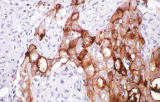

A imunohistoquímica (IHQ) com anticorpos primários CE/IVD é essencial para o diagnóstico e classificação precisos de malignidades ginecológicas e mamárias. Estes anticorpos permitem a deteção precisa de marcadores tumorais e proteínas celulares, apoiando o diagnóstico diferencial e guiando estratégias terapêuticas personalizadas.

Estudos recentes destacam o valor diagnóstico das proteínas do complexo SWI/SNF, particularmente ARID1B, na identificação de malignidades ginecológicas desdiferenciadas e indiferenciadas – tumores agressivos com mau prognóstico. A IHQ de ARID1B oferece elevada especificidade e está cada vez mais integrada em painéis diagnósticos para melhorar a precisão. Painéis com marcadores adicionais também apoiam a diferenciação de sarcomas uterinos, aumentando a exatidão diagnóstica. Evidência emergente sugere que ARID1B pode representar um alvo terapêutico potencial no carcinoma ovárico de células claras, embora as aplicações clínicas permaneçam em fase investigacional.

Anticorpos primários contra recetor de estrogénio (ER), recetor de progesterona (PR), HER2 e Ki-67 continuam a ser a pedra angular da classificação e decisões terapêuticas no cancro da mama. Estes anticorpos estão validados clinicamente e marcados CE/IVD para garantir deteção fiável e reproduzível de biomarcadores – crucial para orientar terapia hormonal e estratégias de tratamento direcionado.